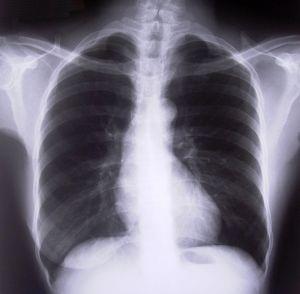

Los pulmones sanos

El edema pulmonar, o también conocido como el agua acumulada en los pulmones, tiene su origen en una insuficiencia cardíaca. Es una enfermedad grave ya que ha sido provocada por una deficiencia del corazón. Además, esta puede derivarse en otras enfermedades también importantes como la neumonía. Sin embargo el edema pulmonar tiene cura, en unComo.com te explicamos cuál es el tratamiento para el agua en los pulmones.